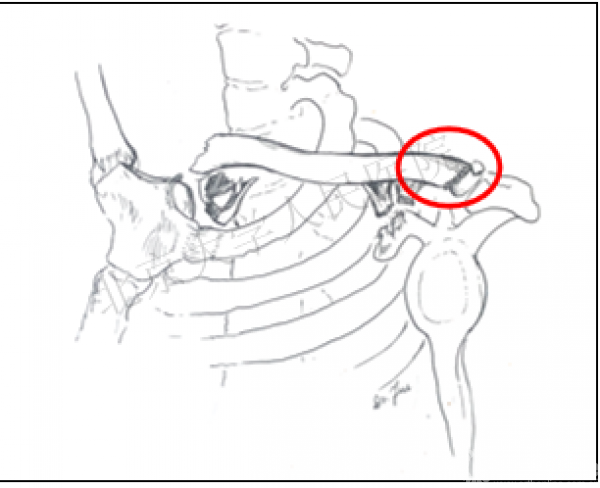

(二)假定机制的示意图

1.F1和F2分别是作用力及反作用力

2.以锁骨下方的第一肋为支点

3.蓝色箭头表示移位方向